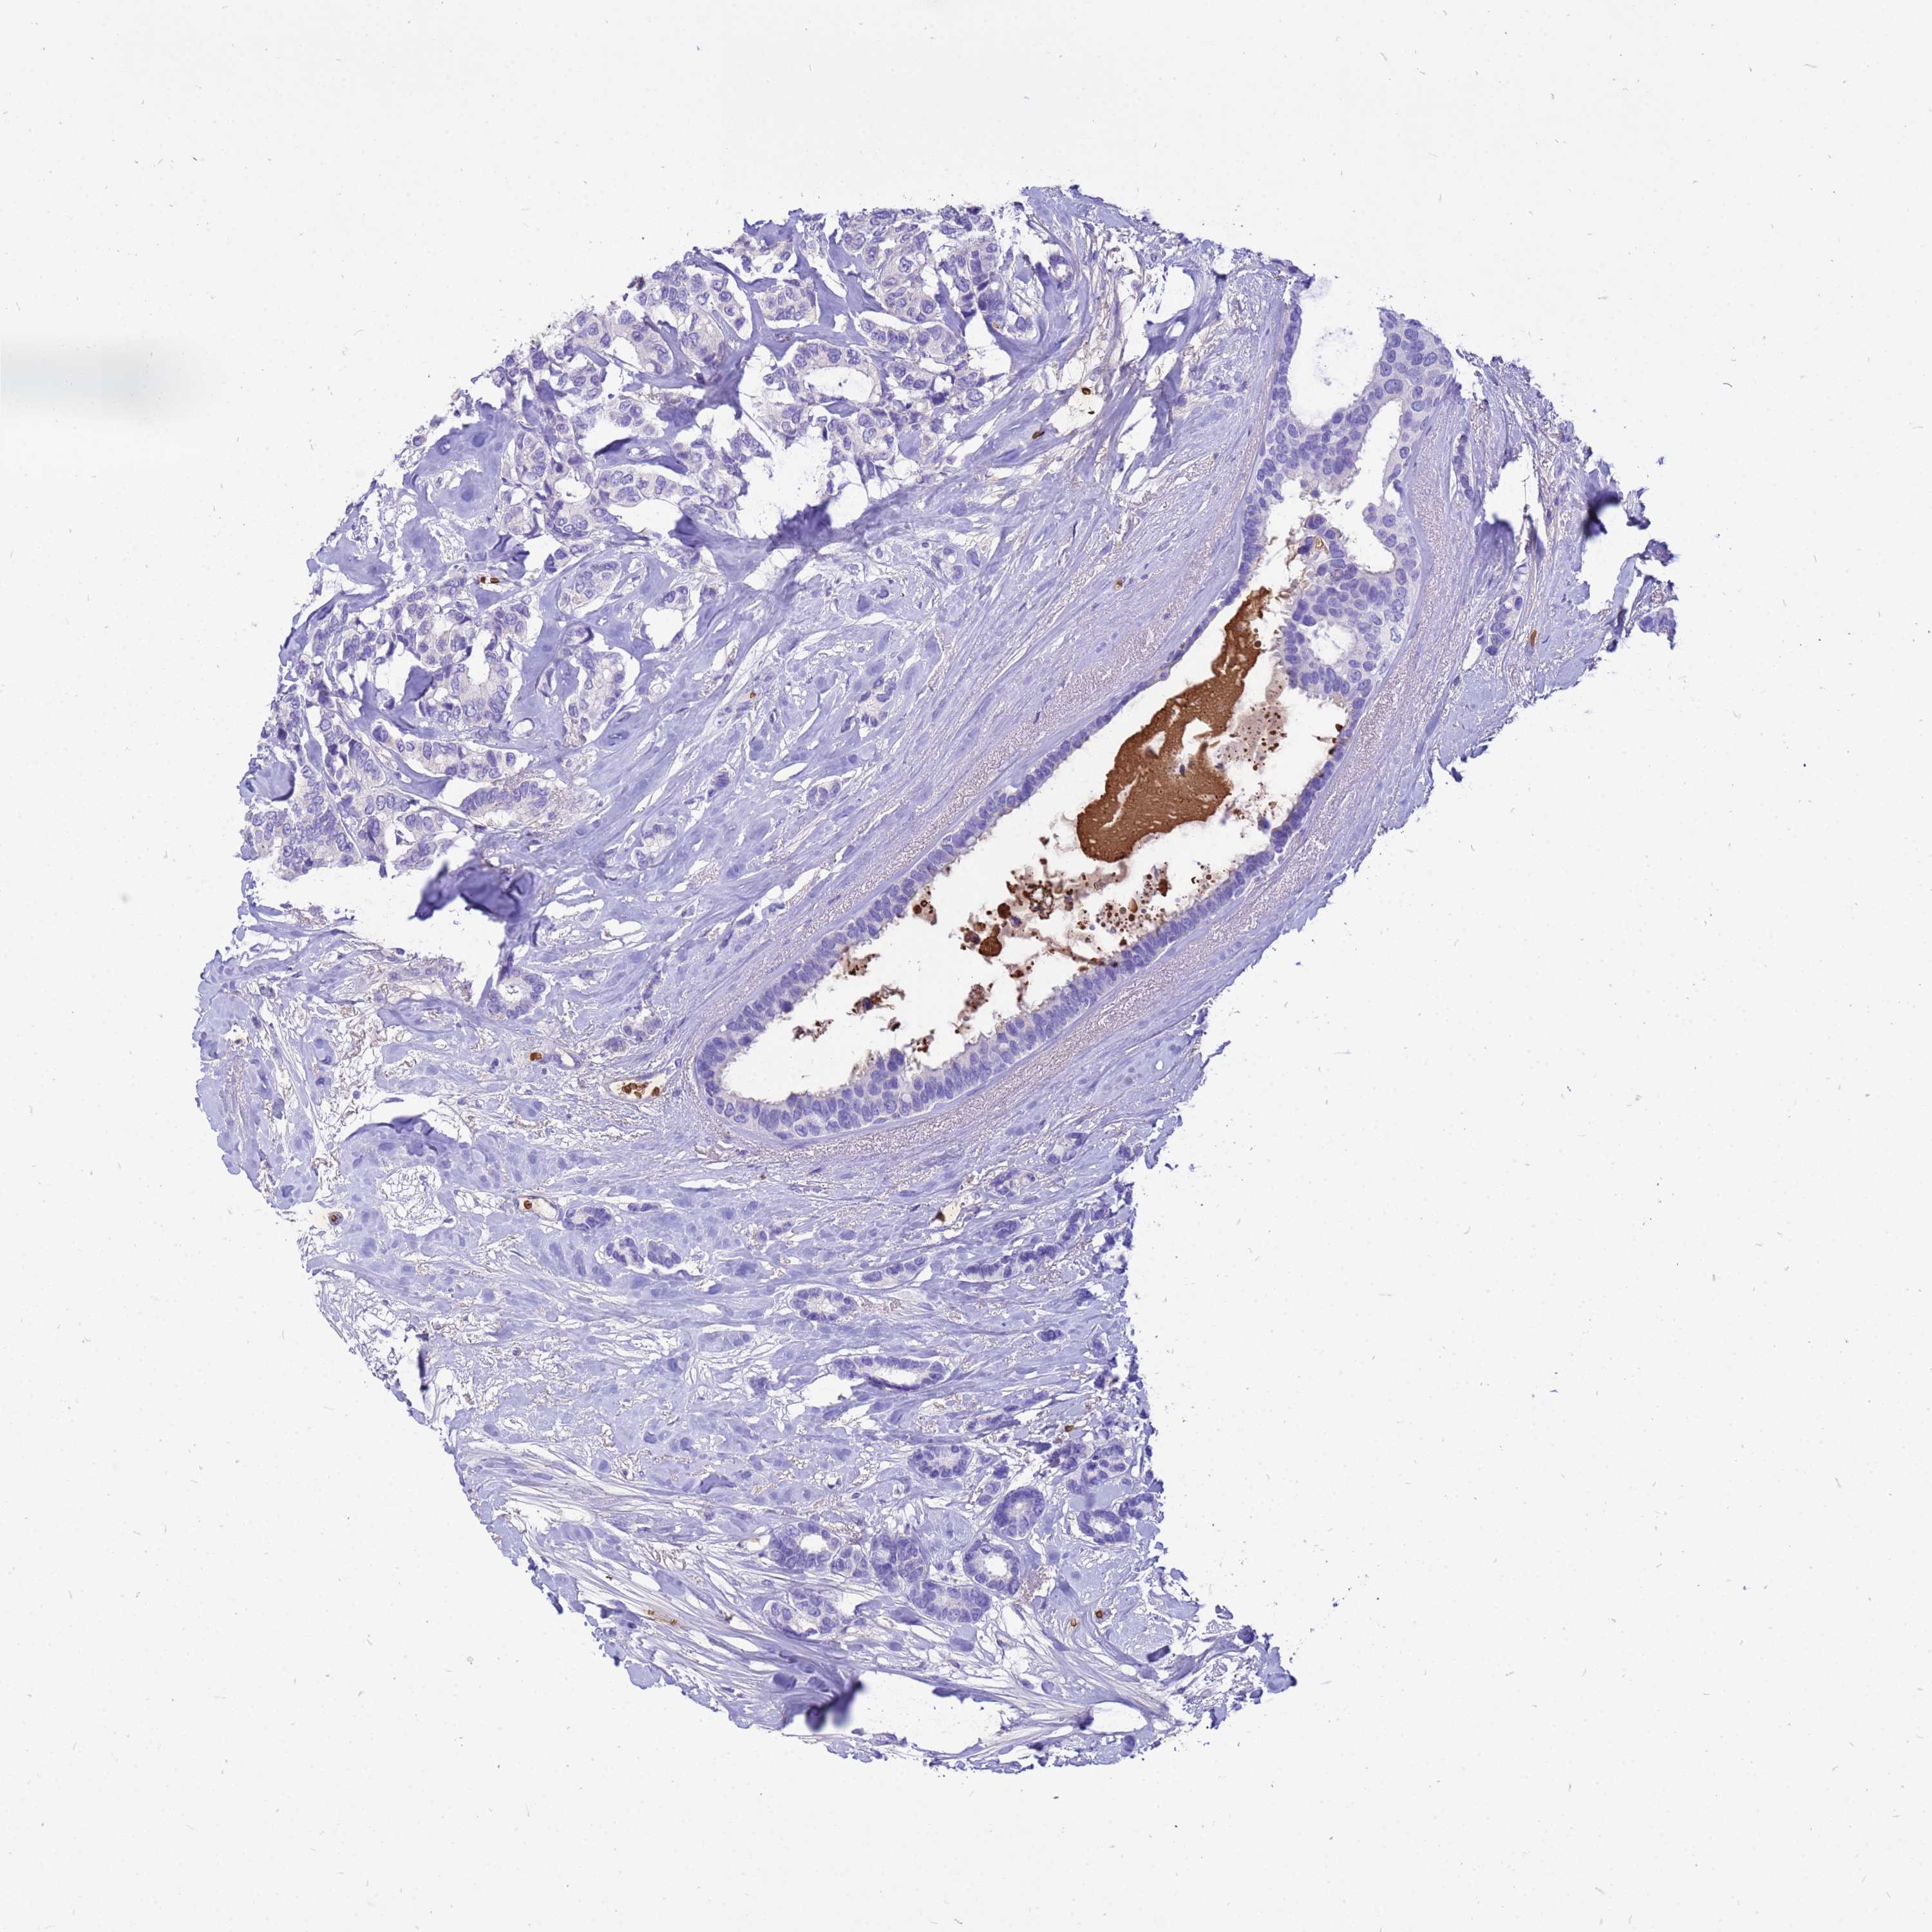

BRCA TCGA BRCA VALIDATION PROTEIN EXPRESSION

ANTIBODIES

AND

VALIDATION